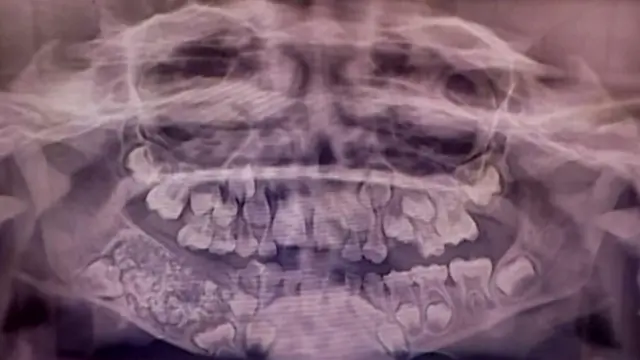

"La radiografía y la tomografía mostraron múltiples dientes rudimentarios en un tejido similar a una bolsa".

Tras una serie de exámenes, los especialistas descubrieron una estructura grande y dura de un peso de cerca de 200 gramos.

Cuando la extrajeron, descubrieron que tenía adentro 526 piezas dentales de entre 1 y 15 milímetros.